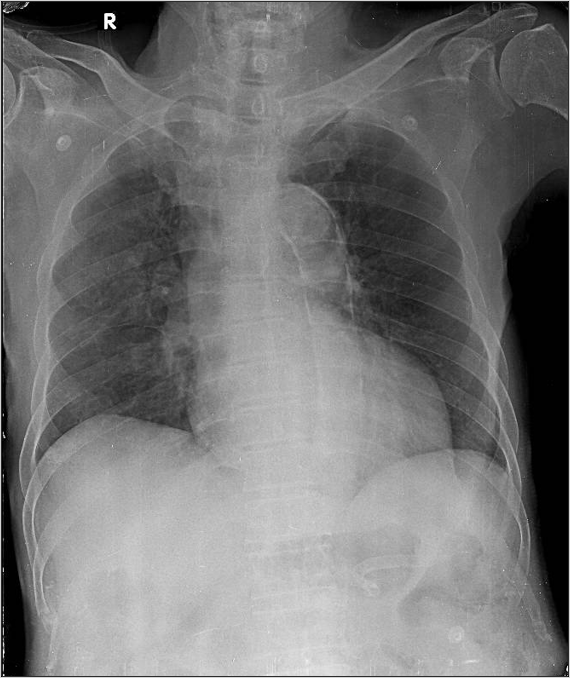

1-Thâm nhiểm phế nang thùy trên phổi (P) 2-Cung động mạch chủ dãn 3-Cung động mạch chủ đóng vôi 4-Tim trái lớn